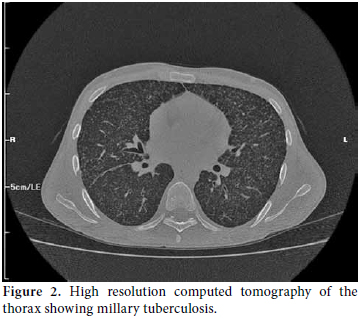

A 22-year-old male patient was presented to the emergency room of our hospital with complaints of fever, headache, and fatigue which had been occurring for 10 days. The medical history revealed that he had been diagnosed as having Behçet’s disease in 2007 and had been using prednisolone since the time of diagnosis. The dosage of prednisolone was increased up to 64 mg/day by the supervising clinician. Cyclosporine-A had been added to the treatment at 100 mg/day two months previously due to eye involvement but was discontinued after one week due to side effects of fever, fatigue, and headache. The patient was prescribed azathioprine at 100 mg/day on the follow-up visit, and he had been using this drug for nearly 10 days prior to being admitted to our hospital. The physical examination findings revealed a body temperature of 39.8 °C, arterial blood pressure of 110/70 mmHg, and a heart rate of 112/per minute. Neck stiffness was minimally positive. He had swelling and sensitivity on palpation in the right scrotal region that had started three months earlier. Laboratory examinations were as follows: leukocyte count 7.400/mm3, erythrocyte sedimentation rate 87 mm/h, C-reactive protein: 13.4 mg/dl in cerebrospinal fluid (CSF) analysis, leukocyte count: 20/mm3, protein: 200 mg/dL, and glucose: 27 mg/dL (blood glucose: 94 mg/dL). There was no growth on the CSF culture. A chest X-ray was normal. Since the CSF findings and physical examination results could not rule out bacterial meningitis, he was started on ceftriaxone 2x2 gr intravenously. He had no regression of complaints in the first week of treatment, and his antibiotic treatment was discontinued. Internal disease and neurology consultations in conjunction with the clinical findings and CSF results led to a diagnosis of neuro-Behçet’s disease. Scrotal ultrasound screening was consistent with epididymitis. A large number of leukocytes were observed in the material aspirated from the testis (90% lymphocyte in nature). Ehrlich- Ziehl-Neelsen (EZN) staining detected acid-resistant bacteria. Treatment with isoniazid, ethambutol, pyrazinamide, and rifampicin was initiated under the diagnosis of testis tuberculosis. Subsequently, chest high resolution computed tomography (HRCT) and brain magnetic resonance imaging (MRI) were done. The chest HRCT result was consistent with miliary tuberculosis (Figure 1), and the brain MRI revealed findings were consistent with tuberculous granuloma and tuberculous meningitis (Figure 2). The vertebral MRI showed that widespread lytic lesions in the vertebra corpuses and the tissue swelling adjacent to the vertebra were consistent with Pott’s disease and spinal granuloma (Figure 3a and 3b). Based on these examinations, the patient was considered to have disseminated tuberculosis (testicular tuberculosis, miliary tuberculosis, tuberculosis meningitis, spinal granuloma, and Pott’s disease). The anti-tuberculous treatment was revised with the ethambutol being replaced by streptomycin. The patient’s body temperature returned to normal on the eighth day of treatment. The patient, whose general condition was observed to improve, is still receiving the treatment.